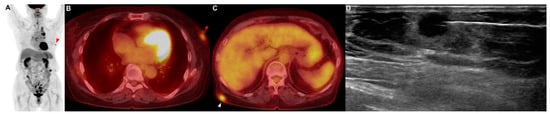

A 79-year-old woman who had never smoked presented with 2 weeks of hoarseness and a history of hypertension and diabetes mellitus. She stated that she had no other illnesses, including cardiovascular, allergic, rheumatic or respiratory conditions. A contrast-enhanced CT scan of her chest showed that a lung mass originating in the left upper lobe had invaded the mediastinum. No endobronchial tumor was observed on the bronchoscopy, and a narrowing of the apicoposterior segmental bronchus of the left upper lobe was observed. Adenocarcinoma was confirmed by brushing cytology of the apicoposterior segmental bronchus of the left upper lobe. If there was no metastasis, the tumor was considered stage IIIB as T4N2. On the PET/CT scan, hypermetabolic lesions were observed in the subcutaneous layer of the middle part of the right back (SUVmax = 4.64) and in the left breast (SUVmax = 3.52) (Figure 3A–C). A core-needle biopsy was performed on the lesion in the left breast (Figure 3D), and the pathological examination reported metastasis of lung adenocarcinoma (TTF-1: positive; GATA-3: negative) (Figure A1C,D). In addition, an excision biopsy was performed on the lesion of the right back, and the pathological examination showed metastasis of the lung adenocarcinoma (TTF-1: positive; ALK: negative; GATA-3: negative; CDX-2: negative) (Figure A1E,F). Additionally, EGFR 19 deletion mutation was detected in this metastatic tissue using an EGFR PCR test. Therefore, this patient was treated with an EGFR tyrosine kinase inhibitor for EGFR-mutated-stage-IV adenocarcinoma.

Figure 3. Patient 3: a 79-year-old woman diagnosed with lung adenocarcinoma with metastases in subcutaneous tissue. (AC) The PET/CT showed a metastatic lesion (red arrowhead) in the left breast. I PET/CT showed a metastatic lesion (white arrowhead) in the subcutaneous layer of the middle part of the right back. (D) The core needle biopsy was performed on the lesion of the left breast.